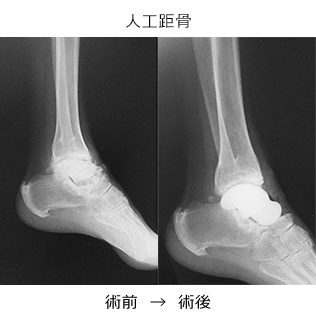

手術療法はそれぞれの部位・変形の程度に応じて、関節温存を目的とした骨切り手術、除痛・変形矯正のための関節固定術、人工関節置換術などが選択されます。

しかし、変形の強い変形性足関節症では、長期にわたり、痛みを確実に取り除くために、手術療法が必要となります。手術療法は関節固定術や関節温存手術、人工関節などがあります。我々は、リング型創外固定を使用した骨切り術による関節温存手術を積極的に行っています。末期の変形性関節症の方に対して関節固定術においても、関節鏡を用いた方法を行うことで侵襲を小さくする方法を行っています。また患者さんの状態に応じて、人工関節手術も行っています。